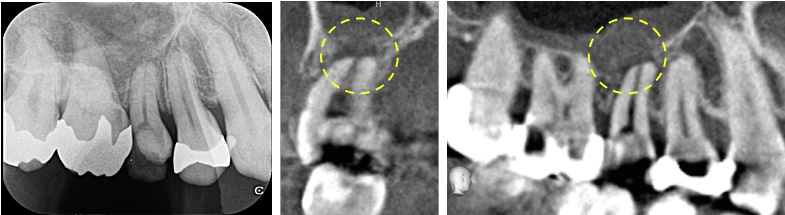

ご来院いただいた時点ですでに歯の神経治療が開始されており、深い虫歯も残存している状態でした。術前のレントゲン・CT画像にて、根の先に大きな黒い影が認めら、上顎洞の骨も吸収しており、上顎洞炎も併発している状態でした。